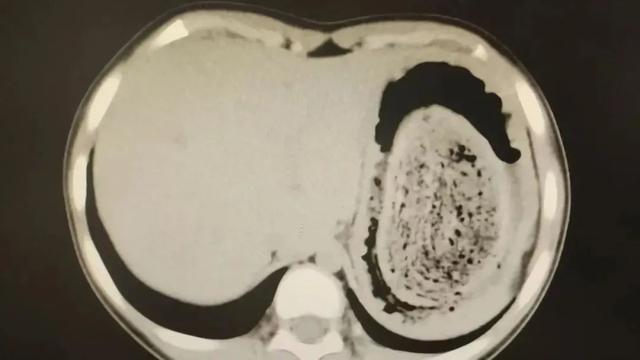

在胃镜帮助下,妮妮胃里的情况逐渐明了。一个滚圆黑色的毛发球混合着食物残渣占据整个胃腔,这些头发相互缠绕形成一个实心的“发石”,此外胃里还有一个鸡蛋大小的溃疡。

症结找到了,就是这个巨大的发石导致妮妮出现营养不良、贫血和闭经。

7月14日,医生进行手术时发现妮妮胃部足有正常状态2倍大,切开胃壁后,一股酸臭味弥漫开来。“发石”混杂着食物残渣,就像一个黑色的小西瓜。整场手术持续2个多小时,最终取出4斤头发碎片。